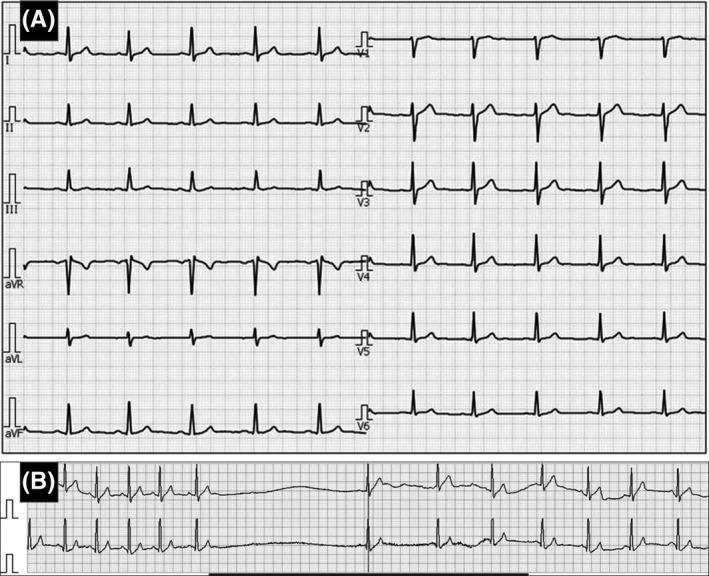

Swallowing syncope is a rare medical condition. Even though it has been known as a neurally mediated syncope, the definitive mechanism of this condition remains unclear. We show in this study an additional case of swallowing syncope and review the 122 reported cases from the literature. A 47-year-old Japanese man had been suffering from recurrent syncopal attacks, when he fainted immediately after swallowing. Holter electrocardiogram monitoring demonstrated a sinus pause (maximum R-R interval of 3.8 seconds) after he swallowed a noodle quickly. A permanent pacemaker was implanted because the frequency of syncope increased.

吞咽性晕厥是一种罕见的医学病症。尽管它被认为是一种神经介导性晕厥,但其确切机制仍不清楚。我们在本研究中展示了另一例吞咽性晕厥病例,并回顾了文献中报道的122例病例。一名47岁的日本男性患有反复发作的晕厥发作,他在吞咽后立即昏厥。动态心电图监测显示,他快速吞咽一根面条后出现窦性停搏(最大R-R间期为3.8秒)。由于晕厥频率增加,植入了永久性起搏器。